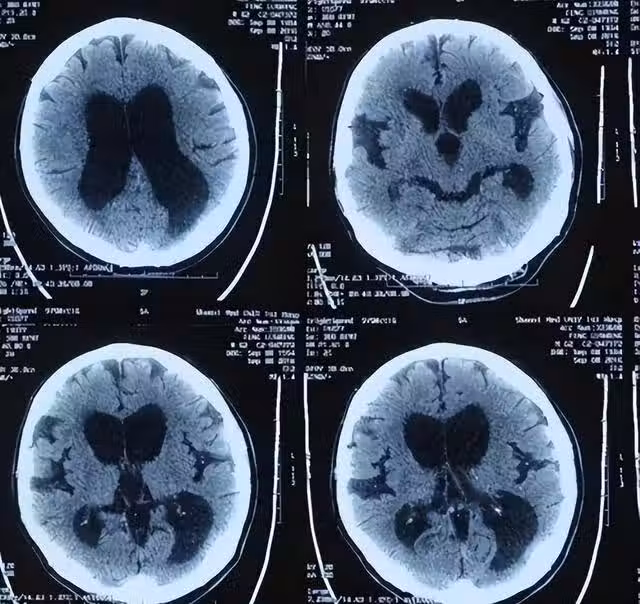

對於正壓性腦積水的治療,最有效的方法是手術,即腦脊液分流。

主要包括腦室引流術和腹腔分流術,目前此技術日漸成熟,能夠有效治癒病症,並且患者術後也不會出現後遺症。